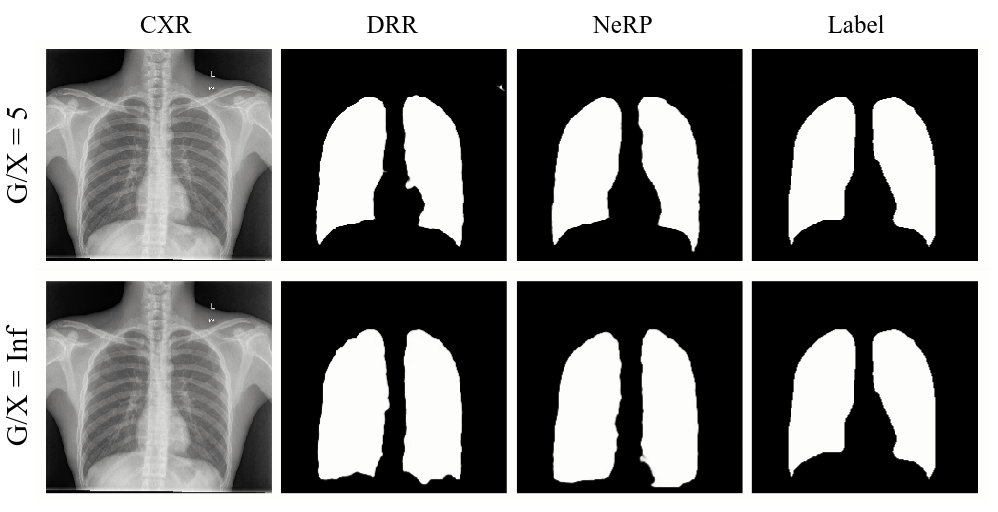

In this assessment, we gradually include portions of Chest XR with Lung annotation to train the U-Net and observe the performance over the quota of having extra annotated subsets of 2D XR data (see Fig. 4). Fig. 5 shows the Dice Scores on the separated test set for this setup. The horizontal axis represents the ratio (G/X) between the number of the generated images and XR images: means that the model was trained from XR only, and Inf means that model was trained from the generated images only. The results indicate that mixing the handful of annotated data with NeRP images yields better performance (up to 2%) over conventional DRR.

Furthermore, we choose extreme cases of Chest XR images with Pleural Effusion Lung Collapse, i.e., lung lobe on one side is filled by high contrast and brightness pixel values. As depicted in Fig. 6, combining NeRP and XR data promotes better lung regions even if the appearance of dark areas is partially missing.